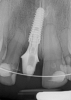

Fig 7. Radiograph showing the patient’s multiple implant restorations.

Figure 7

Figure 6 and Figure 7 depict a mature smile with many implant restorations. An analog impression was sent to the laboratory. The impression was scanned by the laboratory, a model was created virtually, and the implant dimensions and position were defined. The 3D surgical guide was fabricated (Figure 8), allowing the patient to receive his therapy swiftly and predictably. Tooth No. 8 was extracted, and the implant was placed and immediately loaded with an acrylic provisional treatment crown (Figure 9). The screw-retained treatment crown was fabricated in-office from a previously completed diagnostic wax-up.